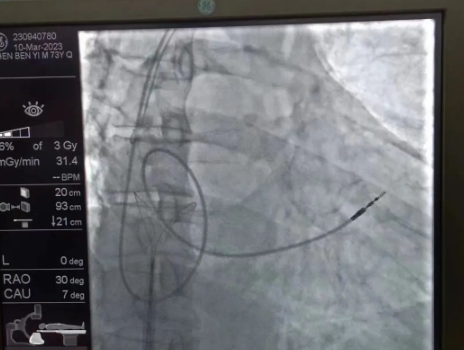

術(shù)中,孫書(shū)紅醫(yī)師首先切開(kāi)起搏器囊袋,游離出起搏器脈沖發(fā)生器,發(fā)現(xiàn)起搏電極完全斷裂,連接于起搏脈沖發(fā)生器,殘端約10cm;考慮患者為起搏依賴(lài)患者,需再次植入新的起搏電極導(dǎo)線,穿刺了腋靜脈,放置導(dǎo)絲;同時(shí),李偉杰教授穿刺了左、右股靜脈,于右股靜脈置入了”抓捕器”,左股靜脈備用臨時(shí)起搏通路,以防術(shù)中出現(xiàn)心跳驟停。為了準(zhǔn)確抓捕到心房?jī)?nèi)的在逃起搏電極,李偉杰教授將導(dǎo)管室的X光機(jī)球管調(diào)整成了冠脈模式,這就意味著在抓捕過(guò)程中,醫(yī)生要比平時(shí)的手術(shù)“吃”更多射線……

在透視模式下,抓捕全憑醫(yī)生的經(jīng)驗(yàn)與手感,一次次嘗試,一次次失敗,在場(chǎng)外觀摩手術(shù)的醫(yī)生同樣為李偉杰教授捏了一把汗,“找到了!”電子屏里抓捕器向在逃起搏電極“發(fā)起進(jìn)攻”,一把逮住并順利拔出一根長(zhǎng)達(dá)58cm的起搏電極。